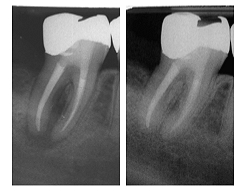

↑ Ernüchterung nach der Abschlusskontrolle: Das Wurzelkanalsystem scheint ordentlich versorgt, wäre da nicht eine ordentliche Portion sealer (in den Fistelgang) überpresst. ↓ Freude bei der Betrachtung des recalls: Der sealer wurde abtransportiert – die apikalen Verhältnisse scheinen intakt.